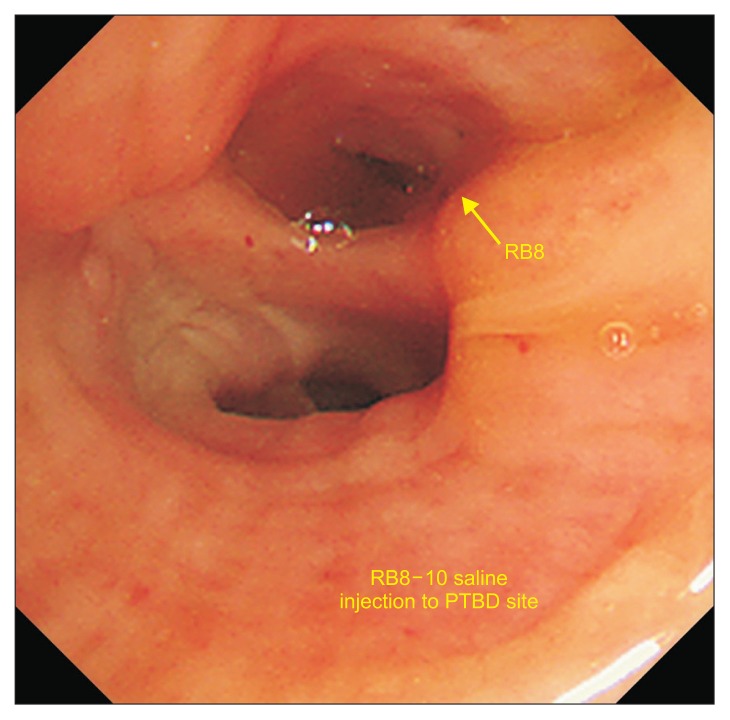

支气管胆道瘘是一种罕见的疾病,定义为胆道和支气管树之间的异常连接。我们报告成功的手术修复支气管胆管瘘。一位78岁的男性接受了手术和几轮经导管动脉化疗栓塞和射频消融治疗肝细胞癌。患者痰液呈绿色,慢性咳嗽数月,经内镜治疗后症状未缓解。我们在开腹和开胸的情况下行右下叶肺叶切除术和网膜固定术治疗支气管胆管瘘。成功闭合支气管胆管瘘,术后胆液消失。

Bronchobiliary fistula is a rare disease defined as an abnormal connection between the biliary tract and the bronchial tree. We report the successful surgical repair of bronchobiliary fistula. A 78-year-old man underwent surgery and several rounds of transcatheter arterial chemoembolization and radiofrequency ablation as treatment for hepatocellular carcinoma. He presented with greenish sputum and chronic cough for several months, and his symptoms did not resolve after endoscopic treatment. We performed lobectomy of the right lower lobe and omentopexy for bronchobiliary fistula under laparotomy and thoracotomy. The bronchobiliary fistula was successfully closed, and the bilious sputum disappeared after surgery.